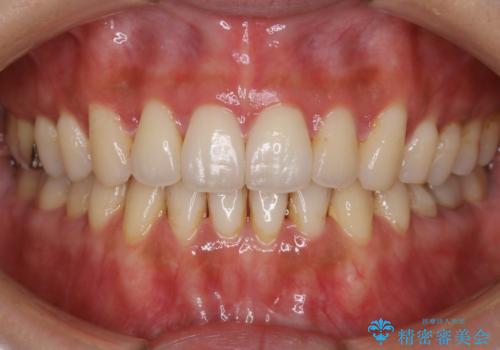

- 歯のガタつきによる見栄えや清掃困難を主訴にご来院されました。

左側の噛み合わせは上の歯が前方に寄ってきてしまっていることが原因のズレがありました。

ガタつき自体は歯列の幅の拡大やディスキング(IPR)でほとんど解消可能でしたが、噛み合わせのズレは歯の移動が必要だったため、左上にマイクロインプラントを使用し噛み合わせの改善とガタつきの解消を同時に進めるという方針をとりました。